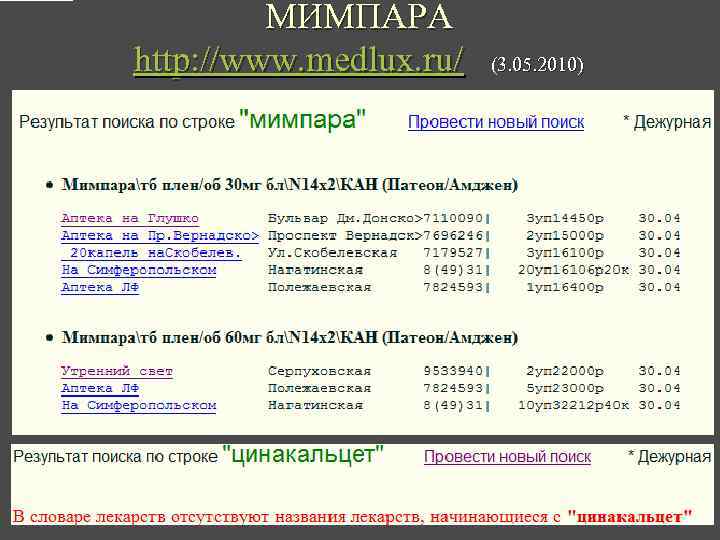

ЦИНАКАЛЬЦЕТ http: //goldpharma. com/? show=search&search_srt=MIMPARA&lang=RUSSIAN (3. 05. 2010)

МИМПАРА http: //www. medlux. ru/ (3. 05. 2010)